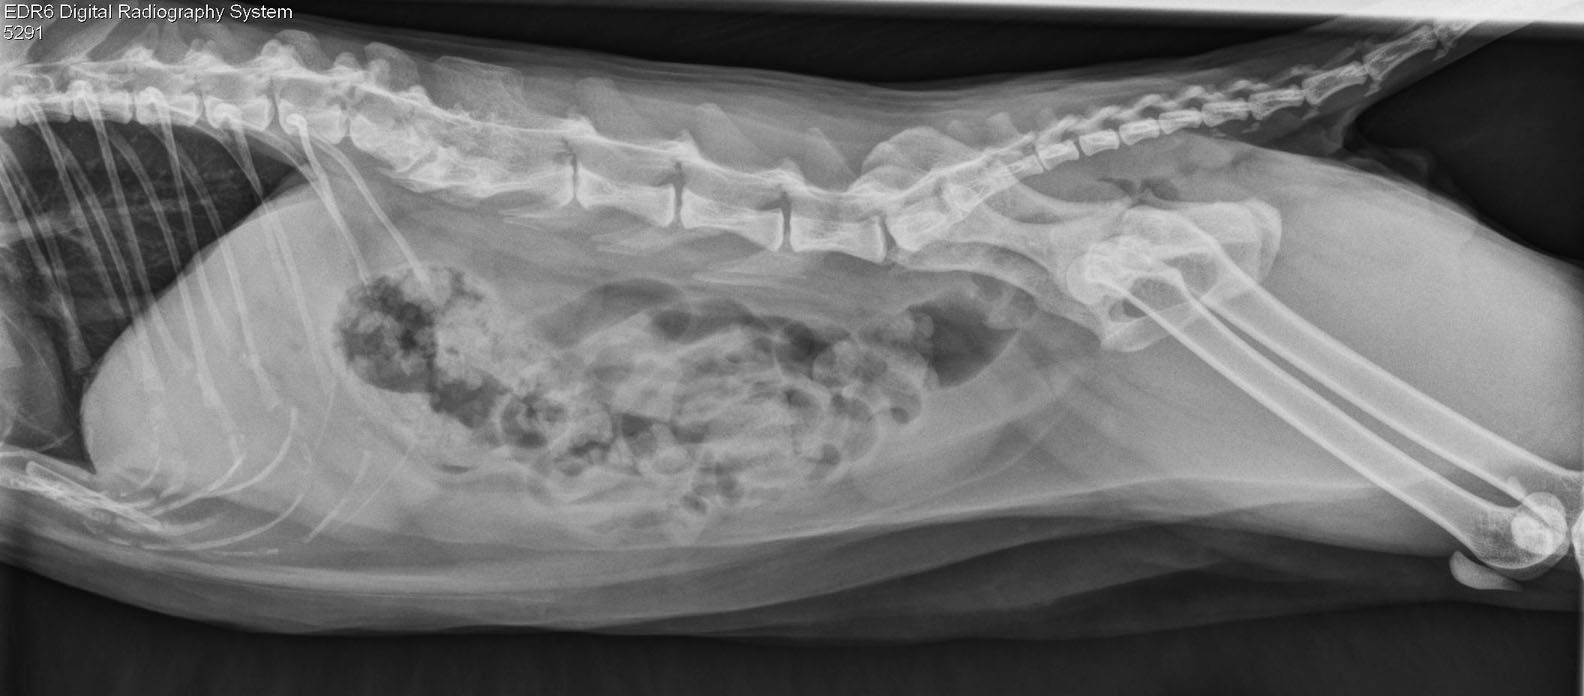

Le spectre vertébral

Pouvez-vous identifier le fantôme malfaisant qui hante cette colonne vertébrale de chat ? Louis-Philippe de Lorimier a eu la frousse en regardant le cliché…

Vite, il faut appeler S.O.S. Fantômes à la rescousse !

Cliquez ICI si vous n’avez pas encore trouvé l’entité ectoplasmique.